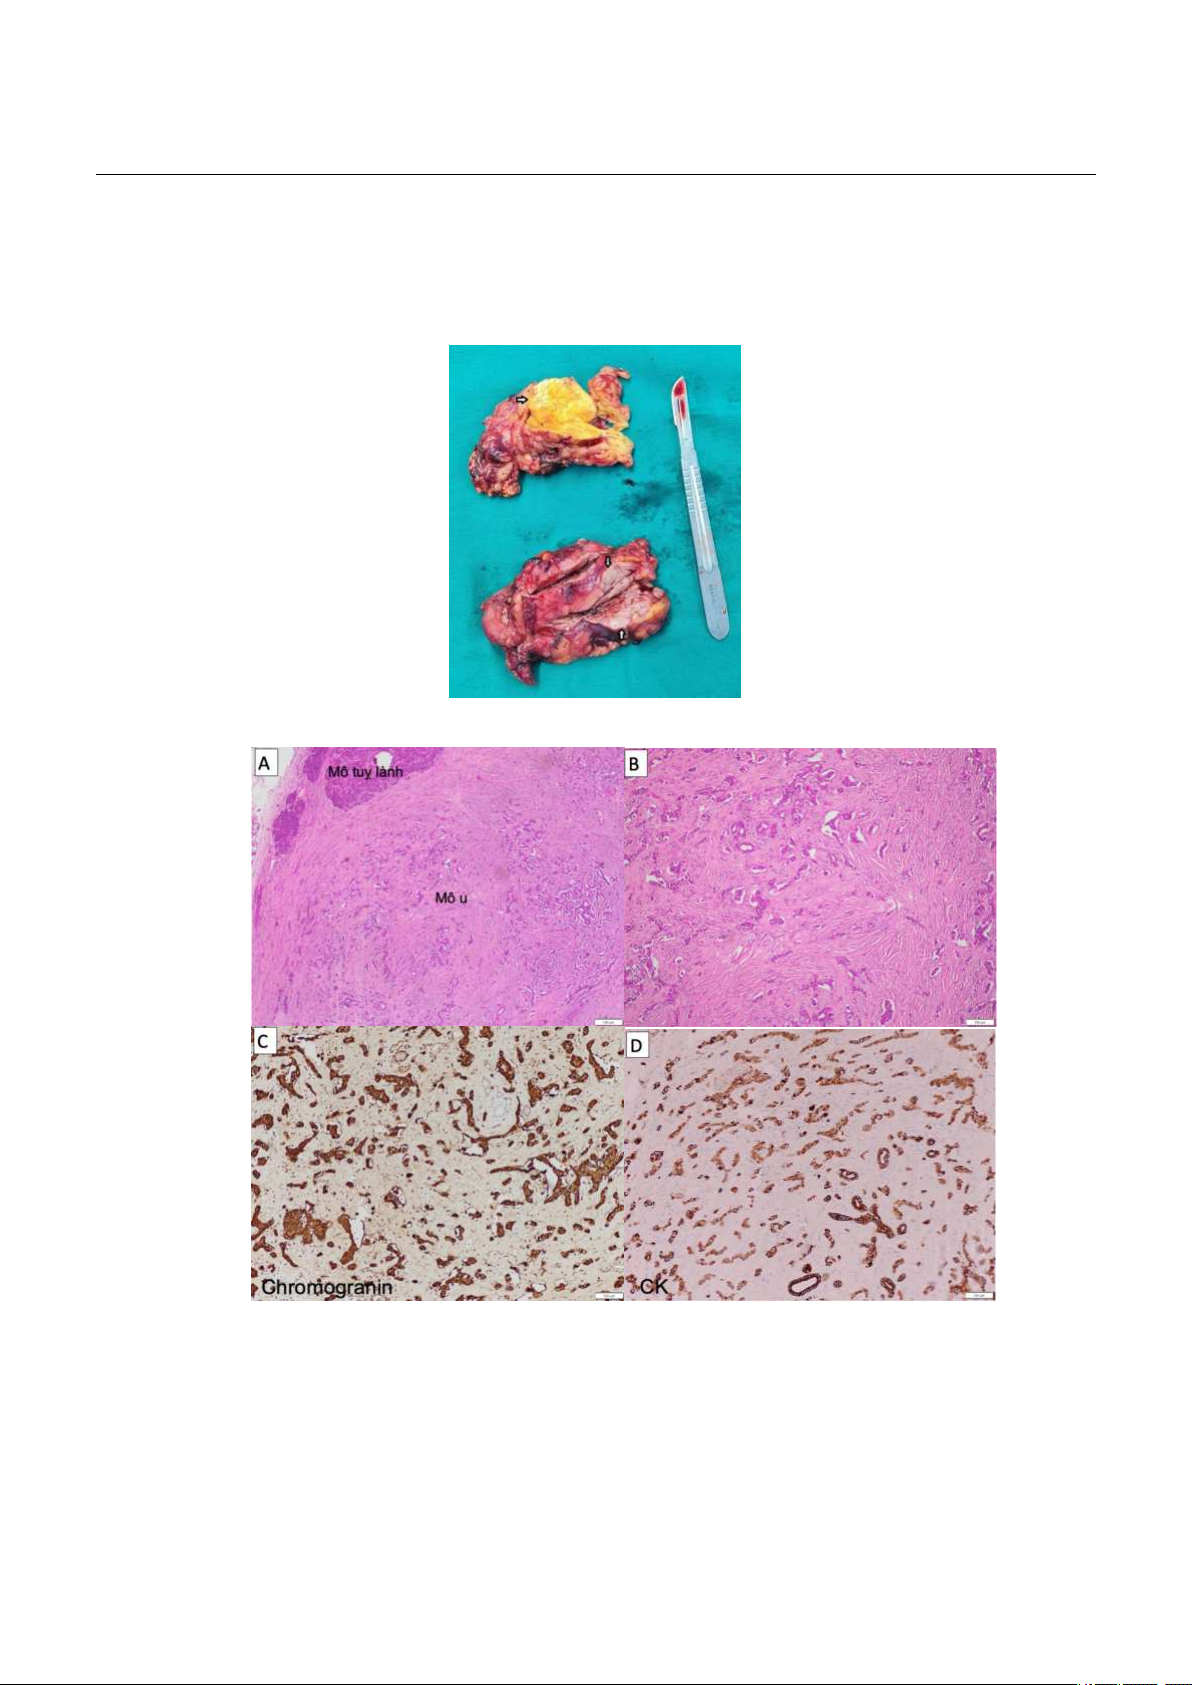

Khối u tuyến yên tiết prolactin: Điều trị nội khoa bằng cabergoline liều khởi đầu từ 0,5mg/ tuần, duy trì 1,5mg/ tuần. Xét nghiệm prolactin giảm dần từ >10000 đến 9097µIU/mL sau 3 tháng. Khối u tụy và tăng sản tuyến thượng thận dạng nốt lớn hai bên nguyên phát: BN đã được phẫu thuật trong 1 cuộc mổ chia làm 2 thì. Thì 1: Phẫu tích vào hậu cung mạc nối thấy đuôi tụy có khối u kích thước 33cm, quyết định cắt thân và đuôi tụy bảo tồn lách. Thì 2: Cắt tuyến thượng thận trái. Hình 7. Hình ảnh đại thể tuyến thượng thận trái (trên) và khối u tụy (dưới) sau phẫu thuật

Hình 8. Hình ảnh mô bệnh học khối u tụy thần kinh nội tiết độ 2 và hóa mô miễn dịch Hình ảnh mô bệnh học mô u và mô tụy lành (A, HE x 10). Hình ảnh mô u tụy gồm các dây, dải tế bào u trên nền mô đệm xơ hoá (B, HE x 100). Hình ảnh nhuộm hoá mô miễn dịch các tế bào u dương tính với dấu ấn Chromogranin (C x 200) và dương tính với dấu ấn CK (D x 200).